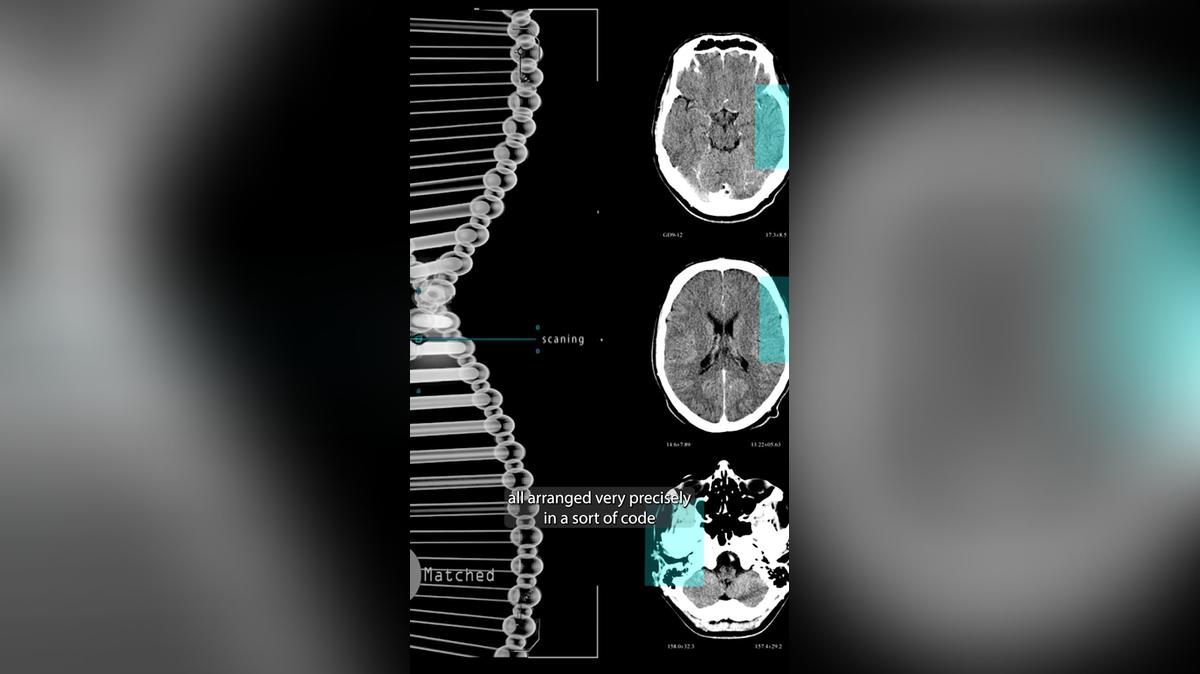

• 26. DNA

26. DNA